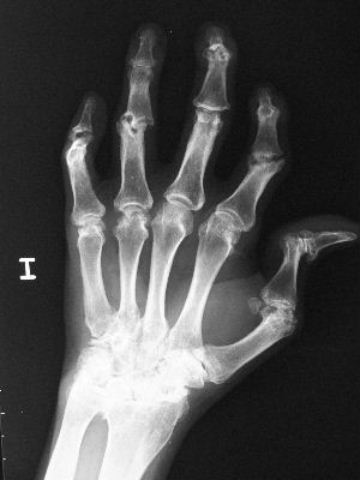

Carpo normal